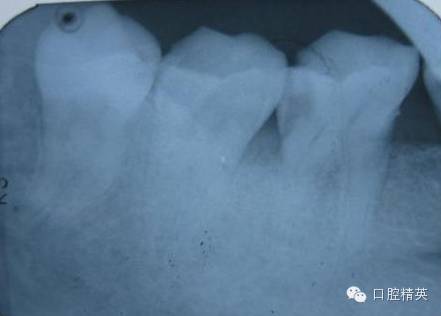

查:46远中邻面洞,冷(+++)探(+++)叩(-)不松。龈正常

诊断:46不可逆性牙髓炎

根管异常狭窄,钙化严重,大量冲洗,润滑。远舌很弯,头痛。

原本以为是4个根,但近中髓底形态不对,超声后果然发现另一个根。